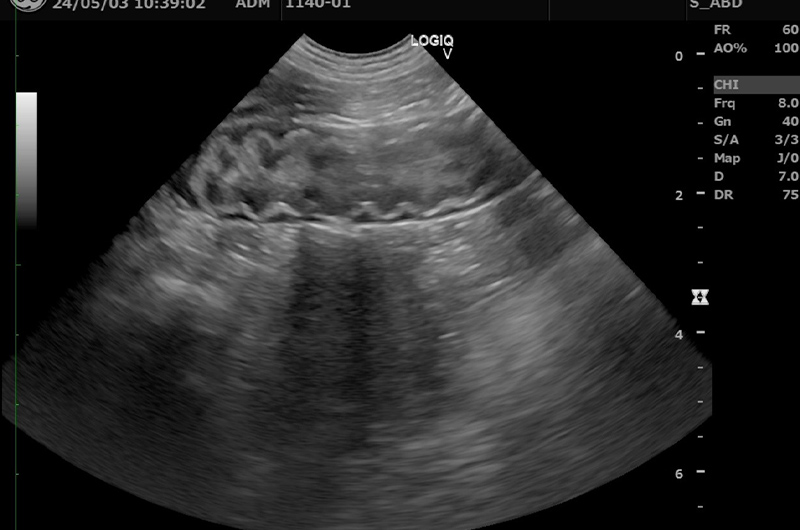

腸炎は下痢、血便、嘔吐、元気食欲低下などの症状を起こす消化器疾患です。原因は様々ですが、細菌や寄生虫の感染、食物アレルギー、中毒物質の摂取、ストレス、不適切な食餌などが挙げられます。下痢の場合は糞便検査を実施して寄生虫の感染があれば駆虫薬で対処し、感染がなく、比較的軽度な症状であれば対症療法により多くの場合は数日で改善します。嘔吐が重度で食欲が廃絶している場合、急性膵炎と呼ばれる命に関わる状態まで悪化していることがあるため、症状が重度であったり繰り返している場合は、血液検査や超音波検査、内視鏡検査を実施して原因を特定した上で治療をします。食物アレルギーや食物不耐性が疑われる場合はフードを変更していただき、フードが合えば遅くとも2週間前後で改善が見られます。

異物による腸閉塞や中毒

好奇心の強い猫ちゃんは、ビニールや毛玉、ヒモ状の異物などを飲み込み、胃腸に詰まらせる事があります。大抵の場合内視鏡や外科的な対応が必要となります。催吐処置で吐き出してくれるケースもあります。異物によって胃腸の通過ができなくなると、必ず嘔吐の初期症状と食欲の不振が続きます。嘔吐しているのに腹部エコーやレントゲン消化管造影により異物が確認された場合、内視鏡または外科手術によって異物を除去しないと症状が解決しません。早期発見早期異物除去が出来れば比較的予後が良い事が多いですが、胃腸に穴があくことで起こる腹膜炎などの合併症があると命に関わる可能性が出てきます。催吐処置、内視鏡、外科手術に対応できますので、吐き戻しがある場合は、動物病院にお問い合わせください。

下痢や血便といった便の症状の際にはまず糞便検査を行います。また嘔吐など上部消化器疾患の症状の経過や重症度、触診の結果によっては腹部エコー検査、血液検査、レントゲン検査をご提案させていただきます。